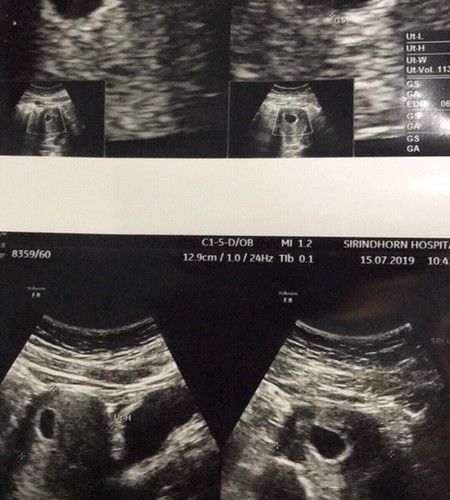

กังวนมากเลยคะไปซาวด์มา ท้อง 7 สัปดาห์ ไม่เห็นตัวอ่อน เห็นแต่ถุงการตั้งครรภ์ไม่เห็นตัวเด็กหมอบอกว่าอายุครรภ์เราอาจจะยังน้อยแม่ๆบ้านไหนเป็นแบบนี้บ้างไหมคะเรากลัวว่าเราจะเสี่ยงต่อการแท้งและท้องลม อีก3อาทิตย์คุณหมอนัดไปซาวด์อีกที แอบกลัวคะเลยขอคำปรึกษาหน่อยคะ

บ้านนี้ซาวด์ตอน 6 สัปดาห์ เห็นน้อง เห็นหัวใจเต้น แต่ซาวผ่านช่องคลอดนะคะ หมอบอกถ้าซาวด์ผ่านหน้าท้องจะไม่เห็นค่ะ

ของเราซาวตอน7สัปดาห์3วัน เห็นเลยเสียงหัวใจมาพร้อม ซาวผ่านหน้าท้องค่ะ

บ้านนี้เห็นถุงตั้งครรภ์ตอน 7 สัปดาห์เหมือนกันค่ะ พอ 8 สัปดาห์ 3 วันก็เจอตัวน้องเลย

ตอน7สัปดาห์ไปซาวก็ไม่เห็นตัวเด็กค่ะ เห็นแต่ถุงตั้งครรภ์